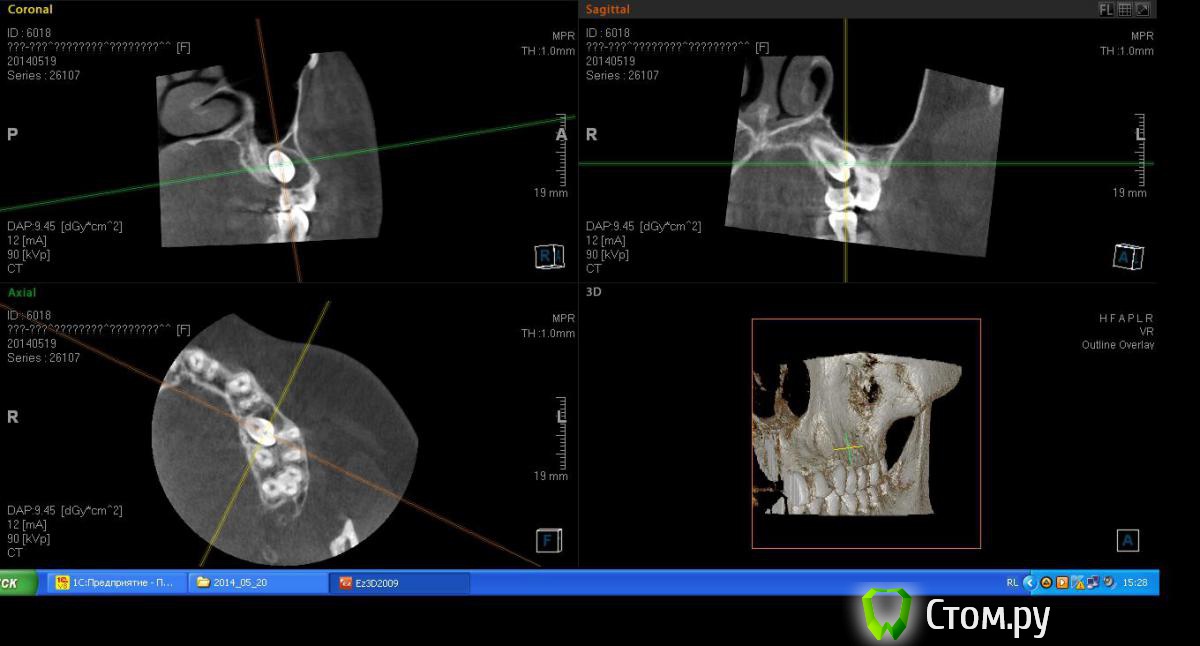

victor57 Опубликовано 29 октября, 2014 Поделиться Опубликовано 29 октября, 2014 Привет, коллеги. Сегодня ортодонт прислал срезы КТ. хочет направить на раскрытие зуба с последующим ортодонтическим лечением. У меня подозрения, что здесь не все так чисто с зубом. У кого какое мнение? Ссылка на комментарий

victor57 Опубликовано 31 октября, 2014 Автор Поделиться Опубликовано 31 октября, 2014 Надеюсь сейчас получиться выложить срезы Ссылка на комментарий

kriokov Опубликовано 31 октября, 2014 Поделиться Опубликовано 31 октября, 2014 залейте если не трудно панорамный вид. Так похоже на ретенированный с остатками фолликула. 1 Ссылка на комментарий